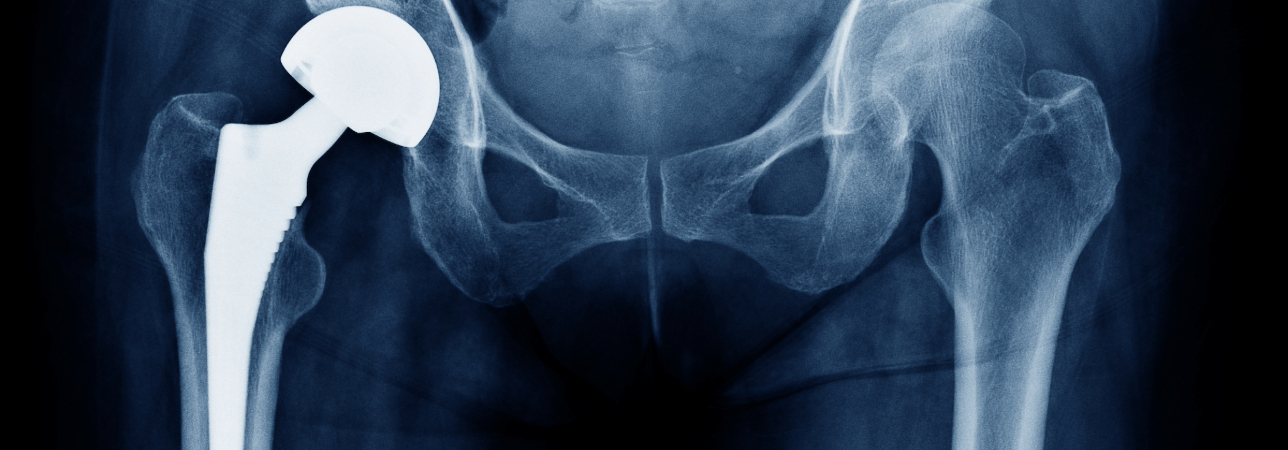

Dr. med. Mauro Molina, a specialist in orthopedic surgery and traumatology of the musculoskeletal system and FMH member, tells us about prosthetic revision surgery, the purpose of which is to provide support to patients who have experienced partial or total failure of a previously performed prosthetic implant.

«Arthroplasty surgery, as it is known, consists of replacing the anatomical structures of the hip or knee, now damaged, with the implantation of mechanical components that allow the joint to return its functionality and resolve pain. As surgical materials and techniques have evolved, there has been a significant increase in the survival of implants over time. In particular, today new prosthesis surfaces allow better fixation to the bone, new generation polyethylene has less wear than previously used, and biomedical ceramic has greater strength; new polyethylene/ceramic, and ceramic/ceramic bearings have a very low wear coefficient and have contributed to longer implant survival.»